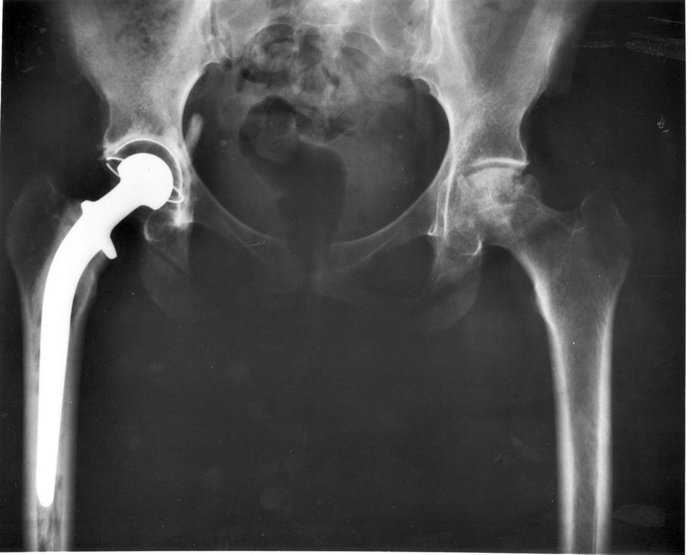

El SCS licita en 6,7 millones el suministro de prótesis de cadera y tiras para detectar glucosa en sangre

Prótesis De Cadera

WIKIMEDIA/NATIONAL INSTITUTES OF HEALTH EEUU

El Servicio Cántabro de Salud (SCS) ha licitado en más de 6,7 millones (6.783.126 euros) el suministro de prótesis de caderas y tiras para detectar la glucosa en sangre, según dos anuncios publicados este viernes y recogidos por Europa Press.

Concretamente, se ha licitado en 3,63 millones el acuerdo marco para la selección de suministradores de componentes para prótesis primarias de cadera (26 lotes) y en 3,14 millones el de tiras reactivas para la determinación de glucosa en sangre (dos lotes).